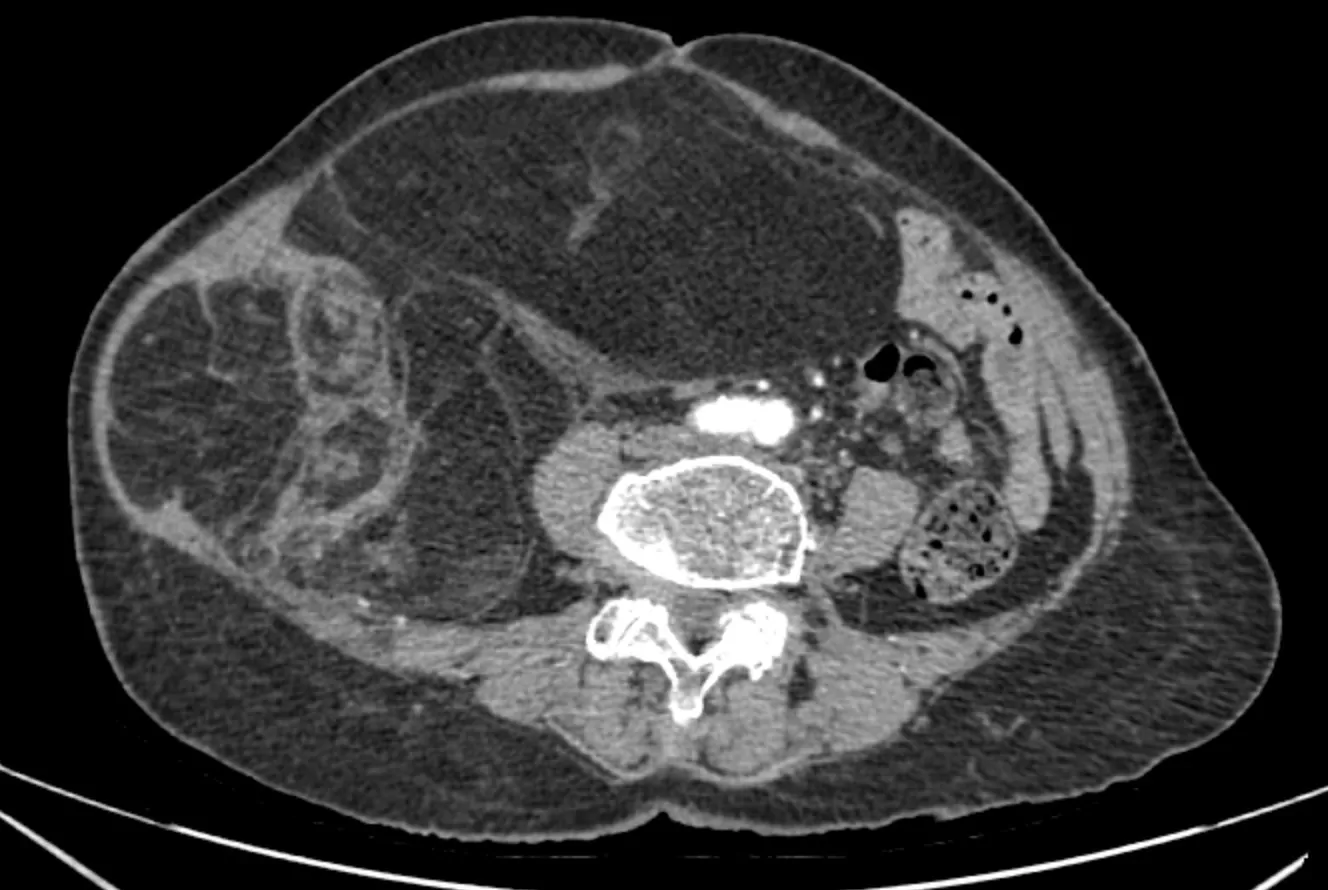

Chẩn đoán hình ảnh (CT ổ bụng có thuốc cản quang) cho thấy khối choán chỗ sau phúc mạc, kích thước 28 × 15 cm, cấu trúc hỗn hợp tổ chức mỡ – đặc , đè đẩy tạng trong ổ bụng nhưng không có dấu hiệu xâm lấn các tạng lân cận. Kết hợp lâm sàng và hình ảnh học, bệnh nhân được chẩn đoán sarcoma mỡ sau phúc mạc.

Phim chụp CT ổ bụng